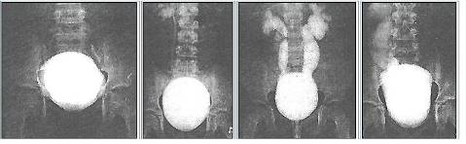

Рентгенограма хворих з СМР

При 1‑й степені закид контрасту з сечового міхура походить тільки в нерозширений сечовід.

При 2‑й степені заповнюють нерозширений сечовід і нерозширений чашечко-мискова система (ЧМС) нирок.

При 4‑й степені і вони стають заокругленими.

При 5‑й степені характеризується масивною делятацією і звивістю верхніх сечових шляхів.

Екскреторна урографія хворого з двостороннім обструктивним мегауретритом

На екскреторній урографії ми спостерігаємо збільшення мисочок, розширення сечоводів, і змінену форму сечового міхура. Стінки якого мають бугристу, нерівну поверхню.